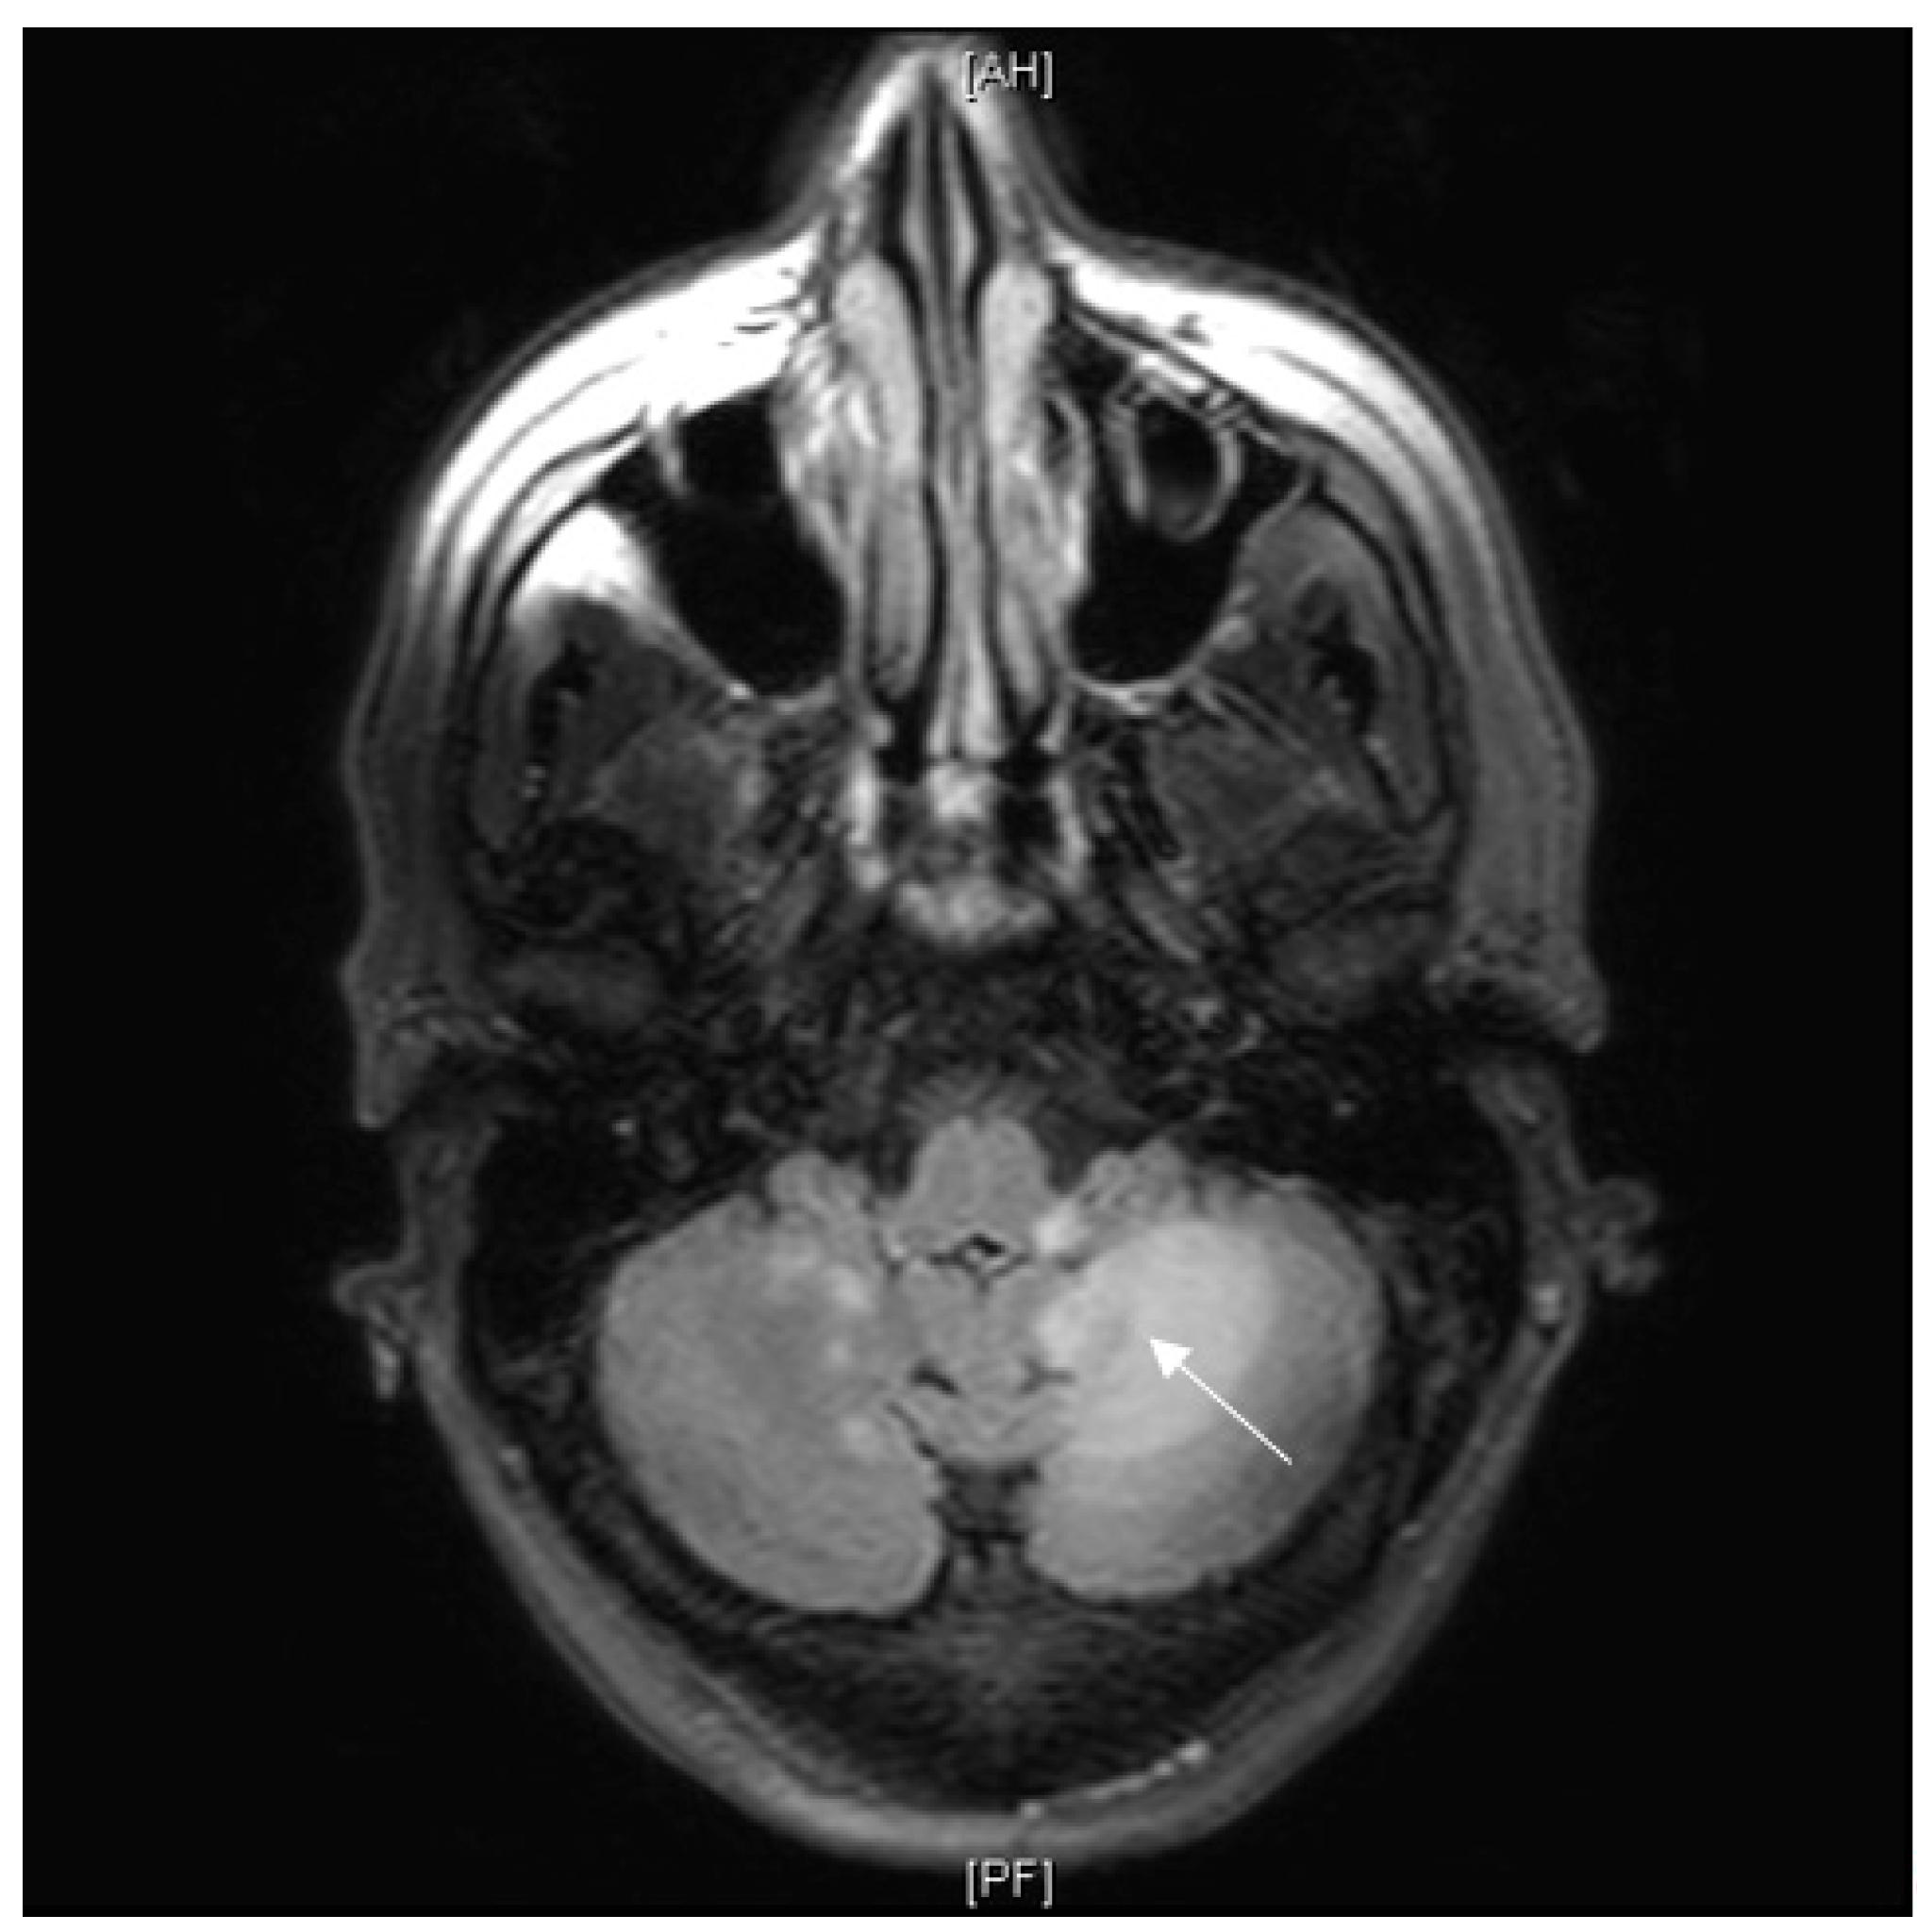

3.7.1. Case Description

| 7* | F | 63 | Caucasian | Bilateral anterior and intermediate uveitis. Granuloma on MSGB. Gait disturbance with multiple supra tentorial demyelinating lesions on FLAIR-weighted sequences. | Corticoresistant uveitis and neurological involvement. | 3 years | Vitroretinal lymphoma. | R-Metho AraC chemotherapy followed by ibrutinib and R-VP16-Holoxan. | The patient died 3 months after the diagnosis [204]. |